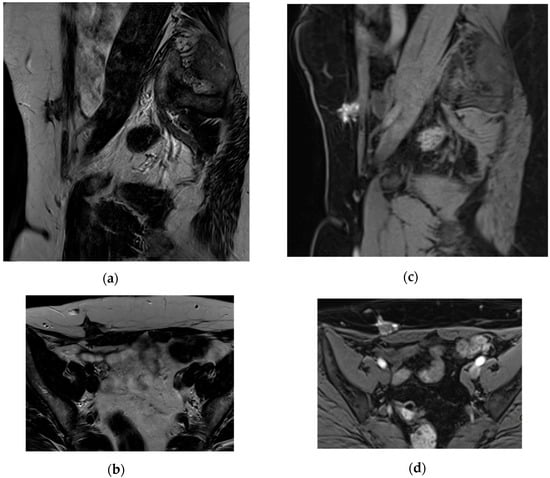

- Radzynski, L.; Boyer, L.; Kossai, M.; Mouraire, A.; Montoriol, P.-F. Pictorial essay: MRI evaluation of endometriosis-associated neoplasms. Insights Imaging 2023, 14, 144. [Google Scholar] [CrossRef] [PubMed]

- Hu, S.; Liu, Y.; Chen, R.; Xiao, Z. Exploring the Diagnostic Performance of Magnetic Resonance Imaging in Ultrasound-Guided High-Intensity Focused Ultrasound Ablation for Abdominal Wall Endometriosis. Front. Physiol. 2022, 13, 819259. Available online: https://www.frontiersin.org/journals/physiology/articles/10.3389/fphys.2022.819259/full (accessed on 17 March 2025). [CrossRef] [PubMed]

- Busard, M.P.H.; Mijatovic, V.; van Kuijk, C.; Hompes, P.G.A.; van Waesberghe, J.H.T.M. Appearance of abdominal wall endometriosis on MR imaging. Eur. Radiol. 2010, 20, 1267–1276. [Google Scholar] [CrossRef] [PubMed]

| Imaging Characteristics | - Mixed (n = 18) - Hemorrhagic (n = 2) - Fibrotic (n = 3) |

| Lesion Locations | - Rectus abdominis muscle (n = 16) - Subcutaneous fat (n = 3) - Combined rectus abdominis + subcutaneous fat (n = 4) |